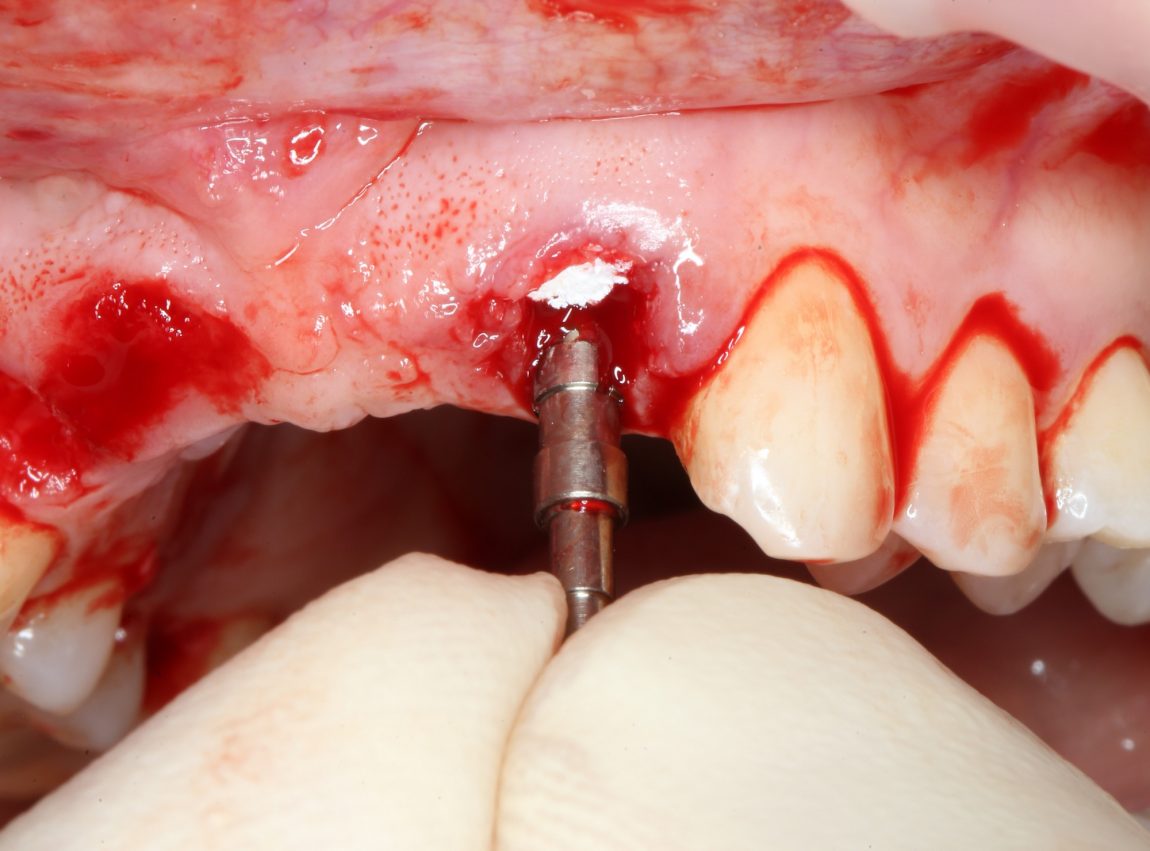

Теперь мы можем оставить десну в покое и приступить к подготовке лунок под имплантаты.

Для этого вспоминаем правила позиционирования и подбора имплантатов.

С имплантационной системой Xive это очень просто сделать — в наборе есть аналоги имплантатов, поэтому мы готовим лунки последовательно, перекрёстно ориентируясь установленным аналогам. Напомню, мы планируем винтовую фиксацию будущего протеза, поэтому правильное положение имплантатов является критически важным для успешной реализации нашего плана:

О правильном позиционировании и подборе имплантатов можно почитать здесь>>, не видим смысла пускаться в подробности. На фото выше — правильное положение имплантатов (ну, или аналога и фрезы) в области боковых резцов.

В процессе подготовки лунки под имплантаты, мы обратили внимание на следующий момент: между финишным диаметром аналога имплантата (3.4 мм) и вестибулярной стенкой лунки удалённого резца остаётся пустое пространство. Маловероятно, что костная стенка такой толщины уйдёт в небытие, но у нас есть пример атрофии в области центральных резцов — там кость ушла. Поэтому мы приняли решение об аугментации лунок:

Обратите внимание, что мы помещаем материал еще до установки имплантатов, а не после неё. Затем, упаковываем его с помощью аналога имплантата, входящего в набор Xive (при отсутствии таковых, можно использовать круглые остеотомы):

Теперь, когда пустое пространство заполнено:

можно установить имплантат. Напомню, мы выбрали Xive S диаметром 3.4 и длиной 13 мм:

Далее, мы повторяем все эти действия с лункой 12 зуба — аугментация с помощью Bio-Oss Collagen, паковка с помощью аналога имплантата, установка имплантата Xive 3.4х13 мм:

Важный момент — как понять, что лунка под имплантат подготовлена правильно? На самом деле, очень просто — в правильно подготовленную лунку имплантат проваливается без вращения больше, чем наполовину: